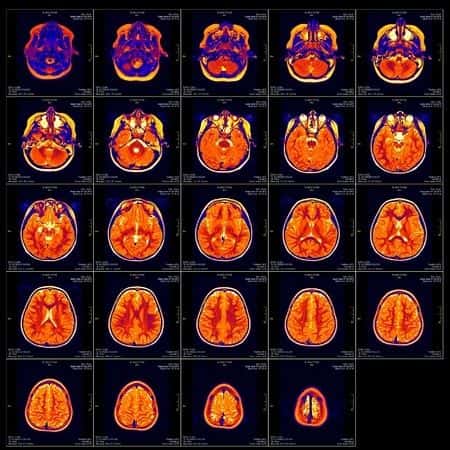

This case takes place in Minnesota and involves a 70-year-old patient who presented to the ER with dizziness and instability, after a period of exercise. She underwent an MRI and nothing showed up except some inflammation in the sinuses. The patient was diagnosed with a sinus infection and was started on treatment. She was admitted for monitoring. Approximately twelve hours later the patient’s condition had deteriorated such that a second MRI was performed which identified a diffuse subarachnoid hemorrhage. The patient underwent surgery to relieve the pressure. She was discharged home after five weeks in hospital and a rehab unit.